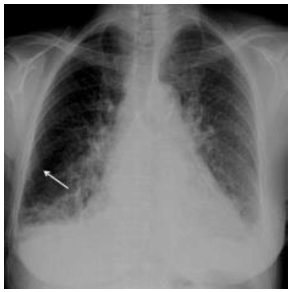

Analise a imagem abaixo para responder à questão.

Considerando a radiografia acima, analise as proposições abaixo.

I. Observa-se que é um paciente do sexo masculino.

II. Radiografia de tórax em PA, demonstra infiltração intersticial reticular bilateral e difusa associada à cardiomegalia.

III. Na porção lateral do pulmão direito identificam-se opacidades lineares perpendiculares à pleura (seta), características de linhas septolinfáticas ou linhas B de Kerley.

É correto o que se afirma em